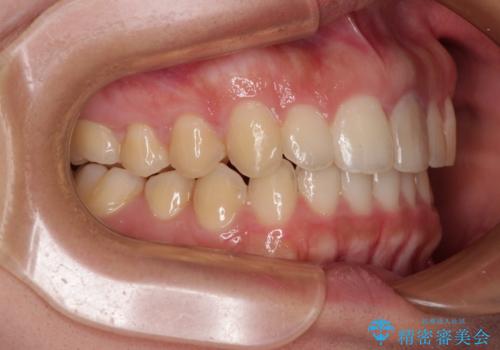

治療途中に上顎前歯が歯髄壊死を起こし、変色してしまいました。

痛みを感じたらすぐに連絡いただくよう伝えていましたが、忘れてしまっており、痛みと変色が発現したことで、すぐに連絡することを思い出されたとのことでした。

今後は、根管治療を行った後に、オールセラミッククラウンにて補綴治療を行う予定です。